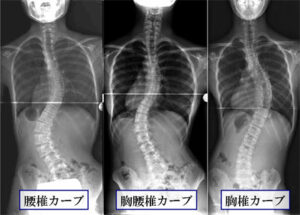

矯正するカーブの場所により方法を使い分けます。後方法は胸椎カーブ、胸腰椎カーブに適応されます。前方法は胸腰椎カーブ、腰椎カーブに適応されます。(図2)